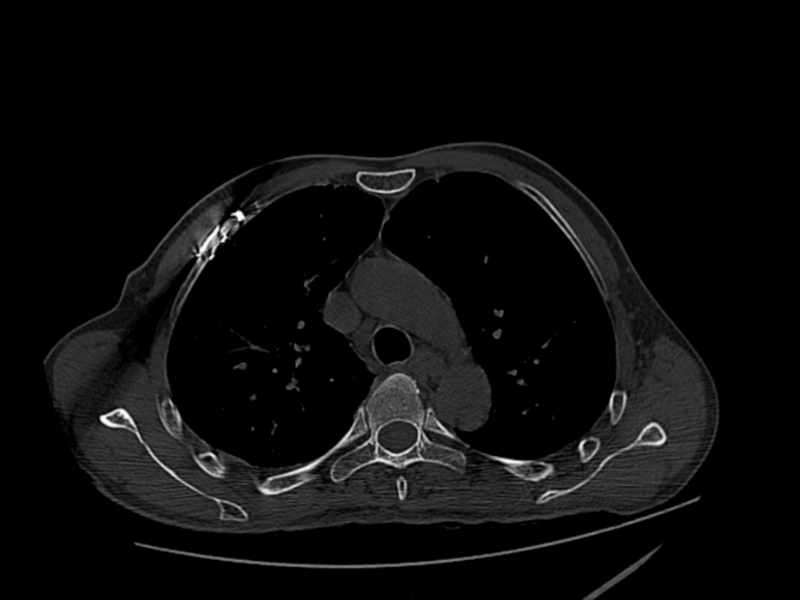

2025年3月7日,對于薛先生來說,是人生的至暗時刻。在工作時,三米高空的重物轟然墜落,將他重重砸倒。當(dāng)急救車呼嘯著沖進(jìn)醫(yī)院時,薛先生已面色蒼白,呼吸急促艱難,每一次喘息都伴隨著痛苦的呻吟,醫(yī)護(hù)人員迅速為薛先生完善身體全面檢查。檢查結(jié)果顯示,薛先生傷情復(fù)雜,其右側(cè)第1-11肋及左側(cè)第1-3、6肋骨折,共有15條肋骨20余處骨折,雙側(cè)創(chuàng)傷性血氣胸、胸腔積液,肺挫傷并破裂,胸骨、胸椎、肩胛骨多處骨折,此外還有臟器損傷等一系列復(fù)雜病癥。這一連串的診斷,仿佛給薛先生的生命套上了層層枷鎖。

△治療前